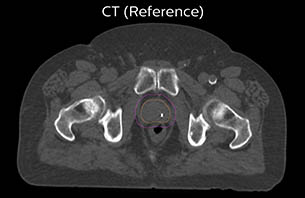

A 77-year-old male with prostate cancer cT3aN0M0, Gleason 8 and PSA 52 μg/L referred to androgen deprivation and radiation therapy with a prescribed dose of 50 Gy to the pelvic lymph node regions and 76 Gy to the prostate.

MR-only simulation workflow The 3D T1W FFE mDIXON sequence provides in-phase, water and fat images in one acquisition. Target and organs-at-risk are delineated on the 3D T2W TSE images. Prostate GTV is shown in orange, PTV in purple. The 3D bFFE sequence is used by the planner to mark the position of the fiducial markers (gold anchors) and contours are transferred to the digitally reconstructed radiographs (DRRs).

Based on the 3D T1W mDIXON images, MR-based density maps (MRCAT) are automatically generated. The VMAT (Volumetric Modulated Arc Therapy) plan is generated in TPS, based on MRCAT as primary image set. During the commissioning phase, dosimetric agreement between MRCAT-based and CT-based dose plans was studied and differences in the PTV dose were found to be minimal (<1% for most patients). Average difference in PTV mean values was 0.8% over the study group (n=62).